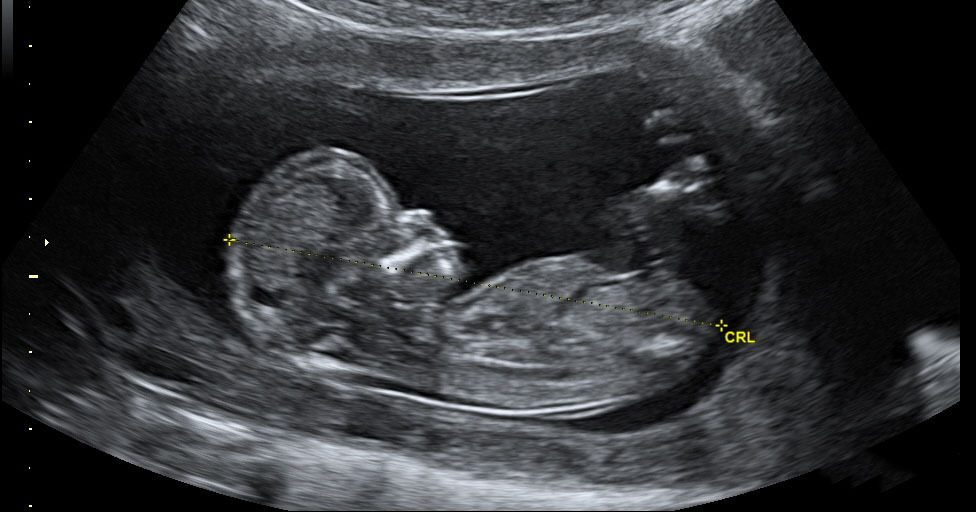

Ahora, cuando el embarazo roza las primeras 20 semanas, la familia ha recibido una notificación en la que en primer lugar piden disculpas “por la demora en contestar su reclamación”. Tras ello, la nota informativa continúa diciendo que “según informes de los profesionales y los datos obrantes en su Historia Clínica, en la primera ocasión que acudió a urgencias se apreciaba un saco intrauterino sin latido. Ello es posible, ya que la edad gestacional era muy baja. Al volver a acudir, seguía sin apreciarse latido cardíaco embrionario, seguía siendo una gestación de pocas semanas, por lo que ya se interpretó como un aborto. Al pasar el tiempo y continuar el embarazo, ya se pudo apreciar el latido. Este error es muy posible que ocurra cuando las gestantes son exploradas de forma iterativa con muy escaso de amenorrea”.

A pesar de todos los problemas que ha tenido que afrontar esta familia, “el niño sigue evolucionando. Ahora está de cinco meses, hasta ahora no ha reportado ningún problema, pero tememos la ecografía de las 20 semanas. Ahí ya se puede empezar a apreciar si puede nacer con algún problema”.